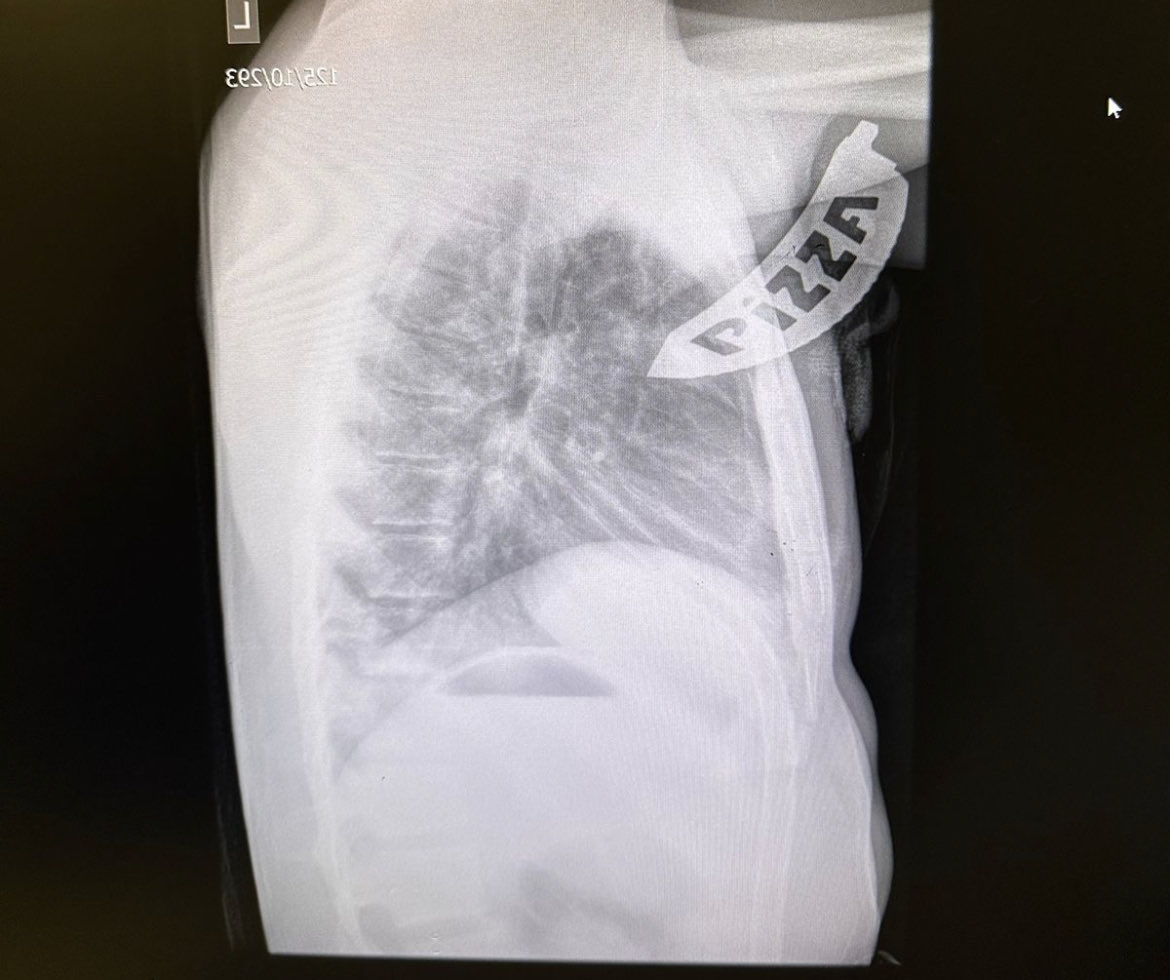

Post-Morten CT scan after fatal blunt trauma. Interesting findings from Jeremy H Levin at #EAST2023. Takeaway messages: Always decompress the chest. Always confirm the airway.

Post-Morten CT scan after fatal blunt trauma. Interesting findings from <a href="/JeremyHLevin/">Jeremy H Levin</a> at #EAST2023.

Takeaway messages:

Always decompress the chest.

Always confirm the airway.